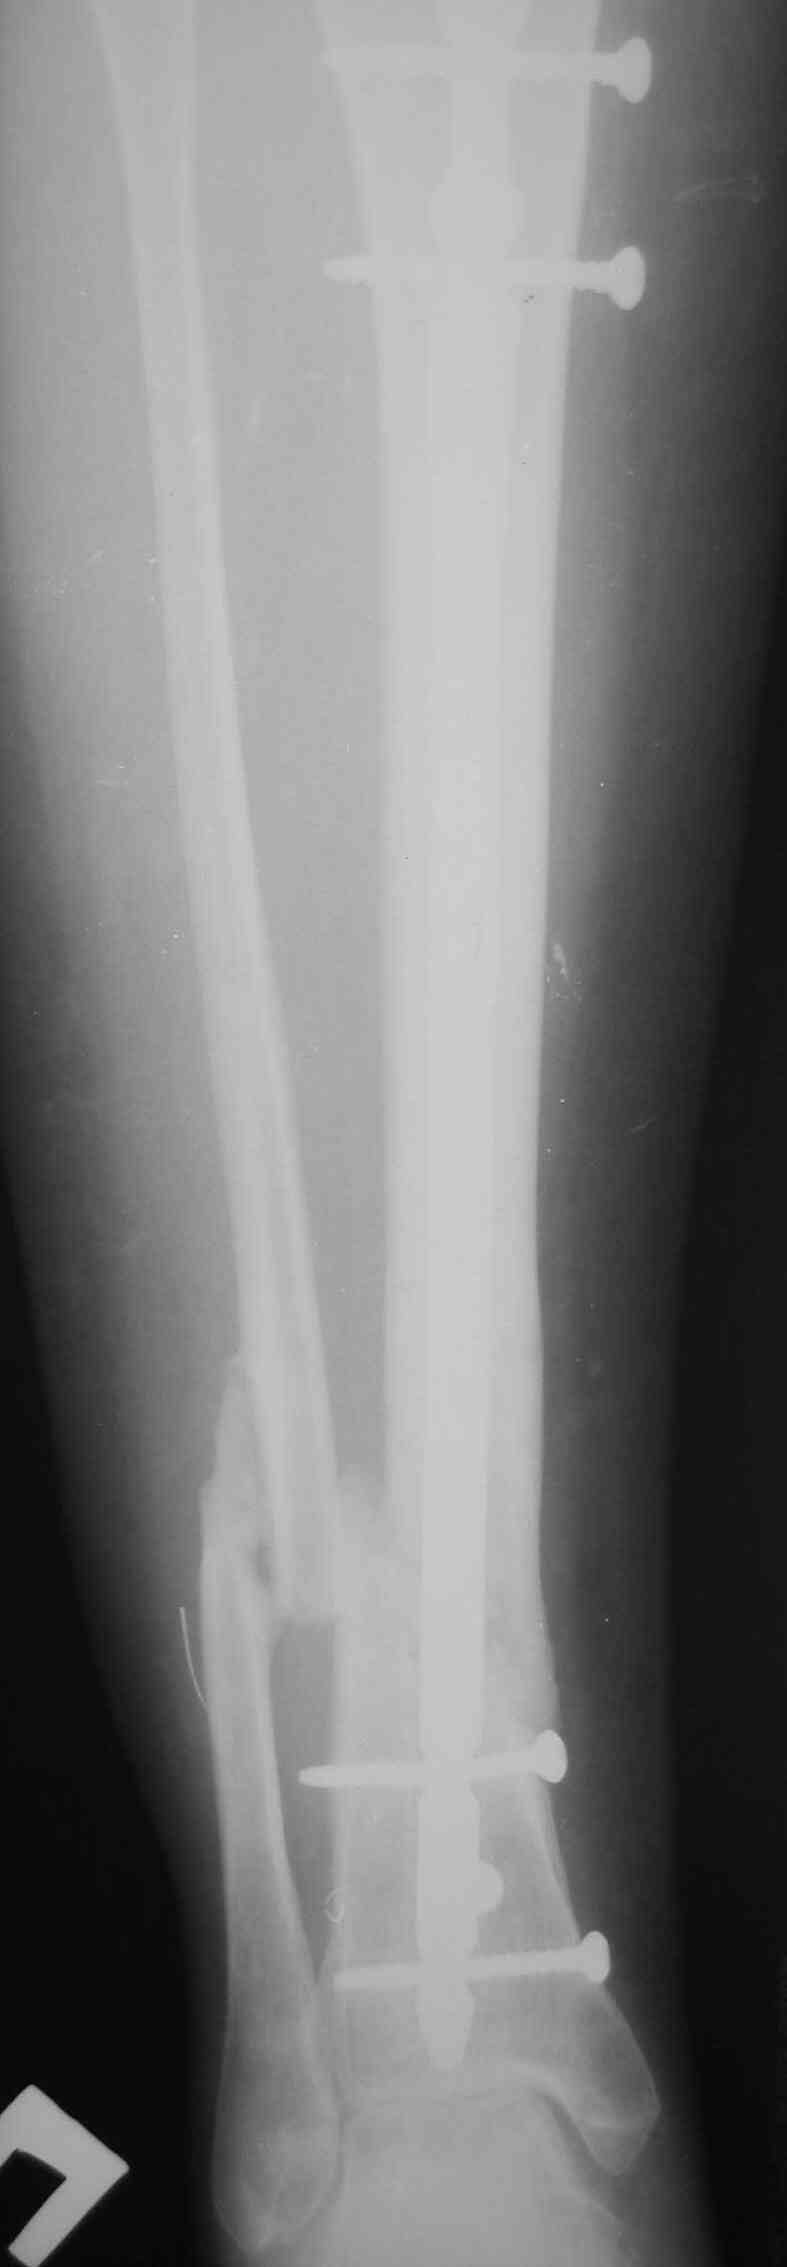

[Ortho] Ложный сустав голени перелом штифта

Р-граммы по теме прилагаю

Имя     : Б.jpg